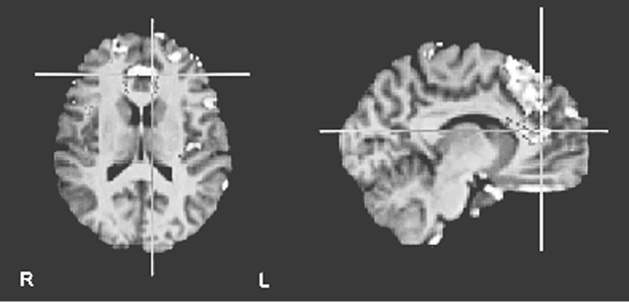

Но это было еще не все. Харрис обнаружил, что оценка «верю» сопровождалась усилением активности в вентромедиальной префронтальной коре (рис. 8.1a ниже) – участке мозга, отвечающем за совмещение факта и эмоции и изменение поведения в ответ на изменение обстоятельств (другими словами, уравновешивание «за» и «против»). «Не верю», в свою очередь, активизировала переднюю островковую долю мозга (рис. 8.1b) – участвующую в том числе и в кодировании негативных реакций, таких как боль и отвращение, и в оценке приятности различных вкусов и ароматов.

Рис. 8.1a. Усиление активности в вентромедиальной префронтальной коре в ответ на правдивые утверждения («верю»), относящиеся к семи разным тематическим категориям (математика, география, автобиография, религия, этика, семантика и события) (по материалам Харриса и др., 2008)